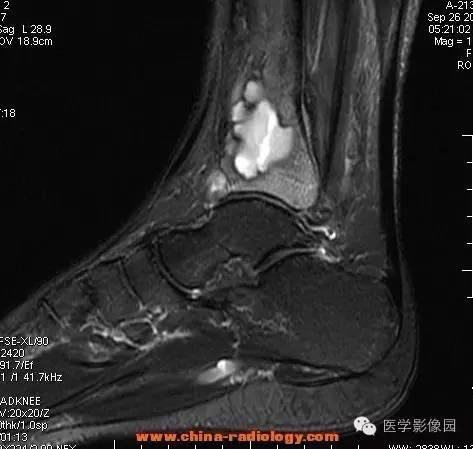

影像学表现:胫骨中下段干骺端不未规则形长T1长T2信号,T2WI见不完整环形稍低信号影,T2脂肪抑制低信号更明显,并见胫骨下段及踝关节后外侧软组织呈弥漫稍高信号,增强明显不均匀强化,增强见低信号环内有环形强化影。

影像学表现:表现为长骨干骺端有椭圆形密度减低区,边缘有清晰的骨质硬化,病变与邻近正常骨髓腔境界清楚。MRI上T1WI呈低信号,少数呈等信号,T2WI多为混杂高信号,增强扫描可见环状强化,强化的脓肿壁薄而均匀。